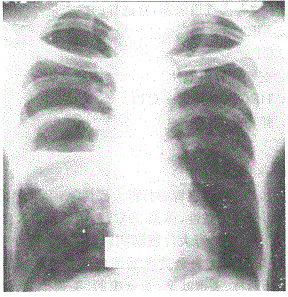

问题 阅读胸片 病灶部位

选项 A.右肺下野 B.右肺上野 C.右肺中野 D.左肺 E.纵隔

答案 C